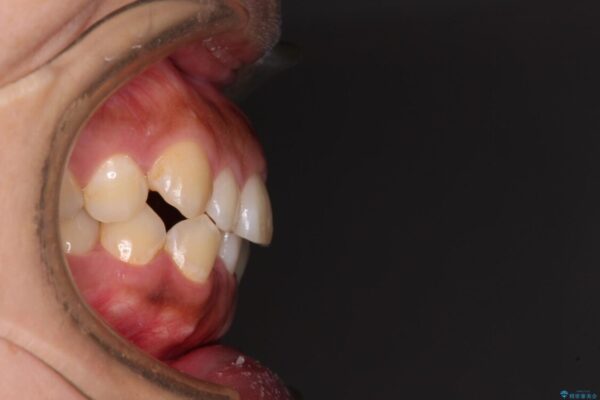

前歯の叢生と八重歯を気にして来院された患者様です。

治療前

• 【モニター】カリエール・ディスタライザーを併用した八重歯のインビザライン矯正 治療前画像